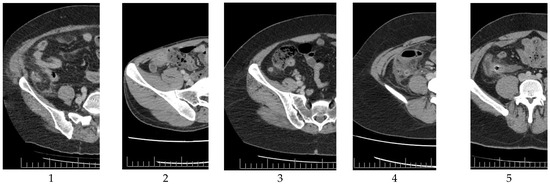

This ensemble approach aimed to leverage the strengths of each classifier while mitigating their individual weaknesses, leading to a more robust and accurate classification outcome. A flowchart including these techniques is shown in Figure 3.

Figure 3. Flowchart of the computer-aided deep learning method. CT—computed tomography; AA—acute appendicitis; SVM—support vector machine; RF—random forest; KNN—k-nearest neighbor.